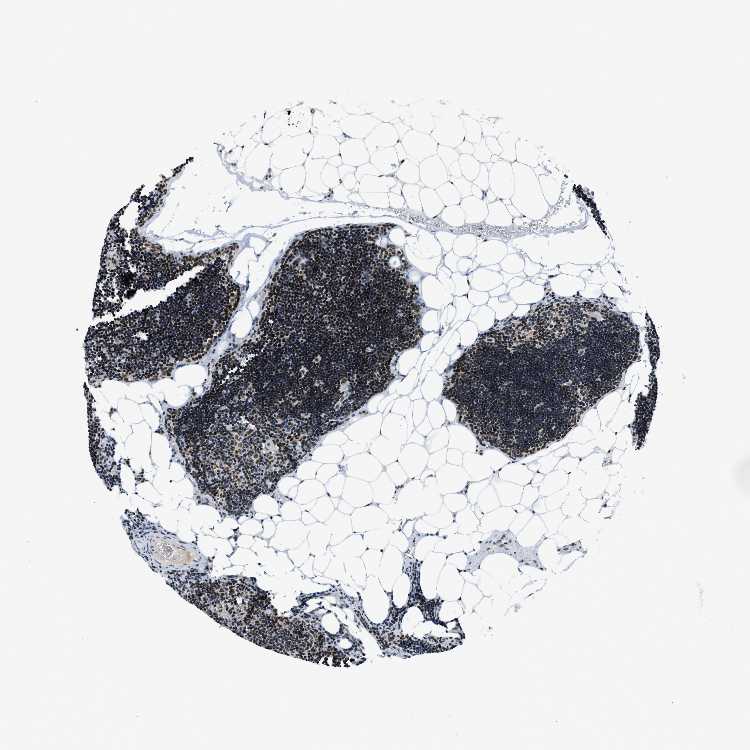

TISSUE PRIMARY DATA LYMPH NODE Show tissue menu

Lymph node

LYMPH NODE - Antibody stainingi

Antibody staining in the annotated cell types in the current human tissue is reported as not detected, low, medium, or high, based on conventional immunohistochemistry profiling in selected tissues. This score is based on the combination of the staining intensity and fraction of stained cells.

Each image is clickable and will lead to virtual microscopy that enables deeper exploration of all samples and also displays staining intensity scores, fraction scores and subcellular localization as well as patient and tissue information for each sample.

Antibody HPA016610

Germinal center cells High

Non-germinal center cells High